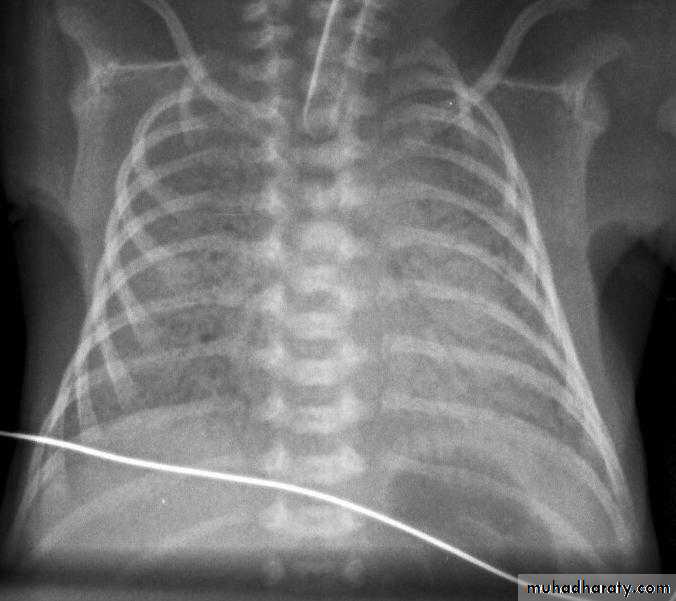

CXR shows whitening of lung with less aeration and reticular feature with ground glass appearance due to atelectases.